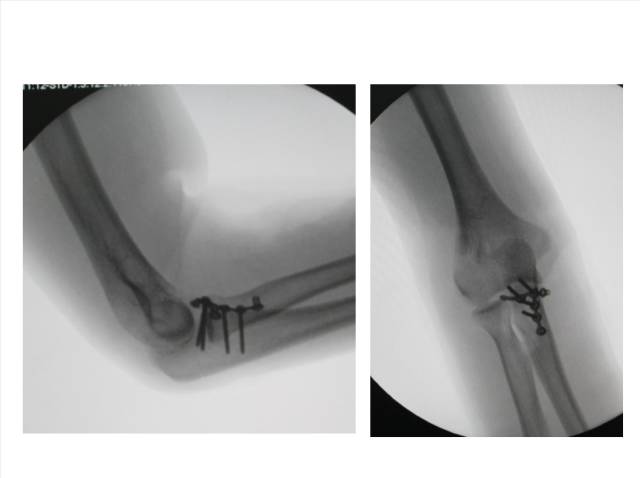

• Ⅰ型和Ⅱ型单纯冠状突骨折,发生后方半脱位的风险很小,允许早期活动

• 即使单纯Ⅲ型骨折,在很小的生理应力下也有可能发生后方半脱位,特别是在屈肘60°~105°,支持对Ⅲ型损伤ORIF